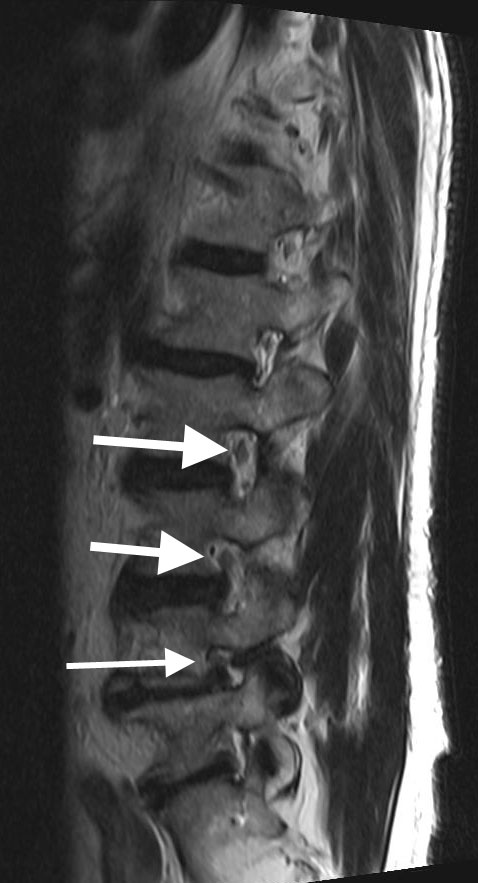

Case Of Grade 3 Foraminal Stenosis T1weighted Sagittal Image Of